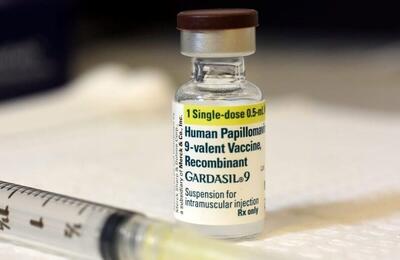

بیماری HPV؛ نحوه انتقال، خطرات، پیشگیری و درمان

در این مقاله، به بررسی نحوه انتقال، خطرات، راهکارهای پیشگیری و درمان HPV میپردازیم و تأثیر رابطه جنسی پرخطر در انتقال این بیماری را به طور تخصصی بررسی میکنیم.

خرید واکسن گارداسیل فقط در بازار سیاه/ همدستی علنی داروخانه و دلالان

برخی از پزشکان متخصص با استفاده از کد ملی بیمارانشان، بدون اینکه آنها درخواستی داشته باشند، نسخه صوری تجویز میکنند و از این طریق، تعداد زیادی واکسن گارداسیل میخرند و به قیمت چندبرابری میفروشند